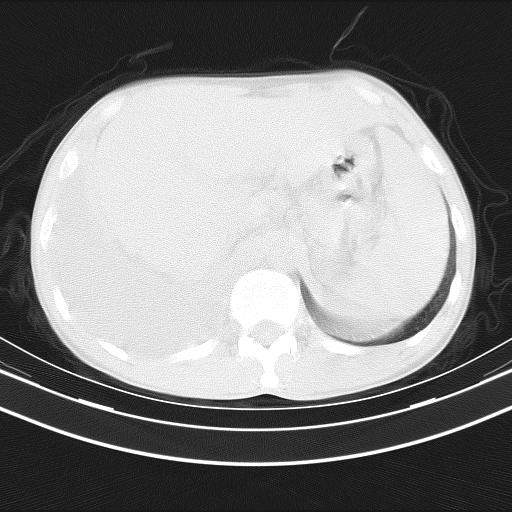

男性,44岁,结核病史多年。现胸闷气短,咳嗽,偶咳血。

右侧胸腔积液

右肺下叶不张

双肺多发结节影最分空洞形成考虑占位不除外结核

双肺陈旧性病变

1、右侧大量胸腔积液伴右肺压缩性膨胀不全,建议抽液治疗后复查 2、两肺继发性tb伴空洞形成。

1)两肺继发性肺结核伴空洞形成,左肺多发性结核球。2)右侧大量胸腔积液伴右肺部分膨胀不全。3)纵隔淋巴结肿大。

吉大一院胸水抽检结果:结核性胸水